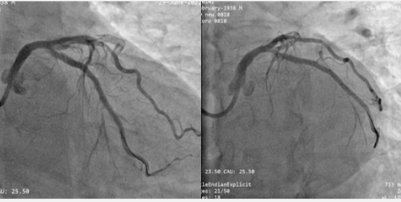

冠脉造影提示:前降支(LAD)支架内完全闭塞(红色箭头),前向血流TIMI 0级。回旋支(LCX)中段狭窄80-90%(蓝色箭头),钝缘支近端狭窄80%。右冠脉(RCA)未见明显狭窄病变。(图2)

图2 患者冠脉造影情况